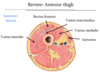

Sartorius

Att: Anterior superior iliac spine, tibia

Inn: femoral nerve

Action: hip abduction, flexion, lateral rotation, knee flexion

Femoral nerve

Innervates sartorius, pectineus, and quadriceps group

Rectus femoris

Att: Anterior Ilium, tibial tuberosity

Inn: femoral nerve

Action: hip flexion, knee extension

All adduct, flex, and medially rotate hip

All originate from pubis

- Gracilis

- Adductor magnus, longus, brevis

- Pectineus

Obturator nerve

Innervates adductor group (except pectineus)